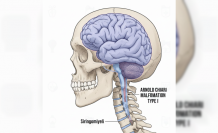

Apert Sendromu Nedir Belirtileri ve Tedavi Süreçleri

Nadir görülen genetik bozukluklar arasında yer alan Apert sendromu, kafatası kemiklerinin erken kapanmasıyla kendini gösteriyor. Kraniyosinostoz (kafatası kemiklerinin erken kaynaması) olarak adlandırılan bu durum, bebeğin kafa şeklinin normalden farklı gelişmesine yol açar. Genellikle FGFR2 genindeki mutasyon nedeniyle ortaya çıkan sendrom, el ve ayak parmaklarında yapışıklıkla karakterize edilir.